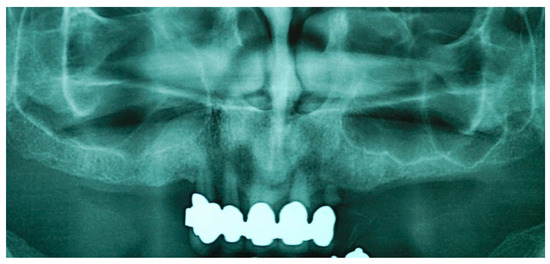

2.1. First Step: Complete Fixed Rehabilitation

2.2. Second Step: From FDP to Implant-Supported Overdenture